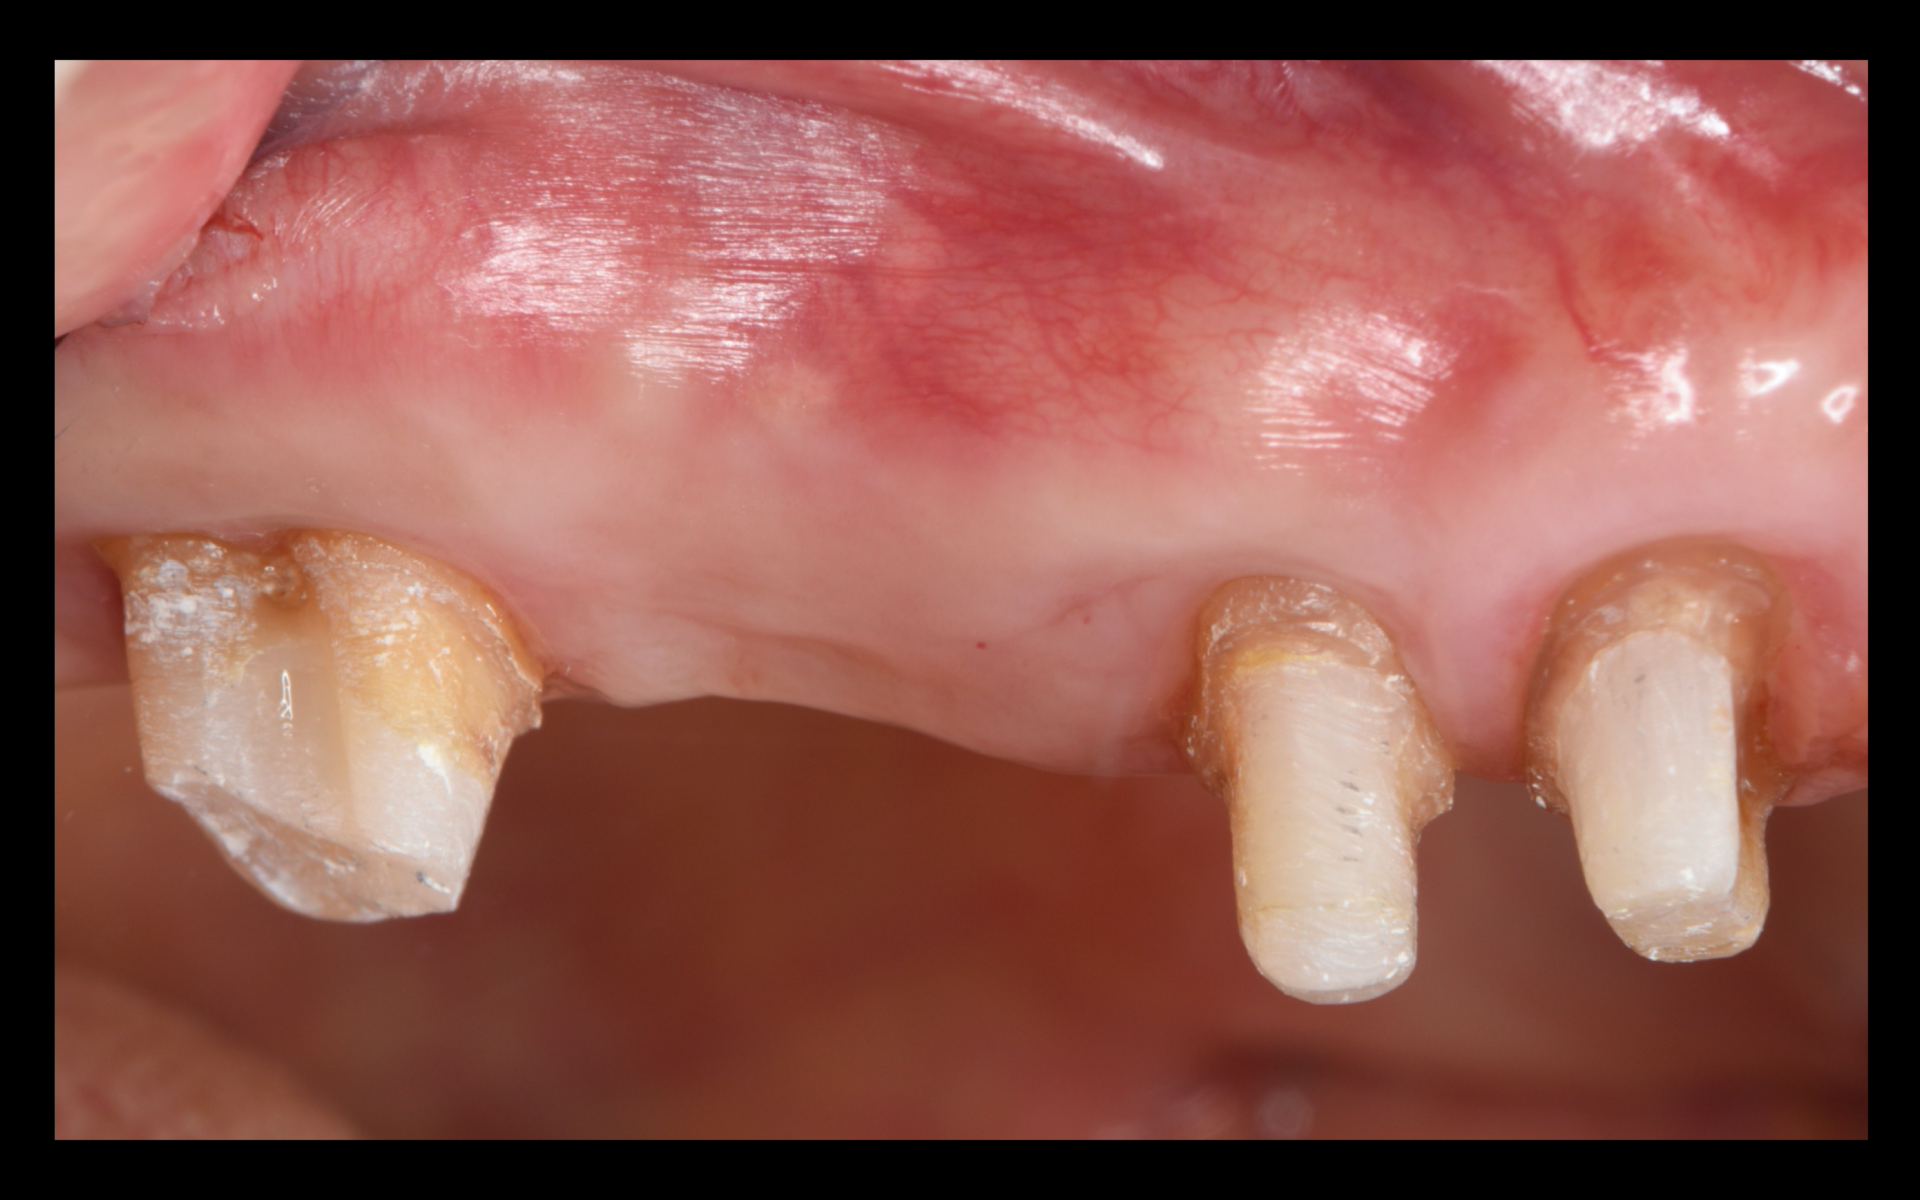

歯周外科から5ヶ月後の写真。歯周外科した全ての歯が表に出て、歯周ポケットも改善された状態。ここでもう一つ歯の延命に繋がる大事なポイントがあります。黄色の矢印の部分です。フェルールといい、1.5~2mm確保されていると、歯が破折する抵抗性を得ることができます。根尖側移動術を行うことで、このフェルールを獲得することができ、安心して補綴(被せ物)をすることができます